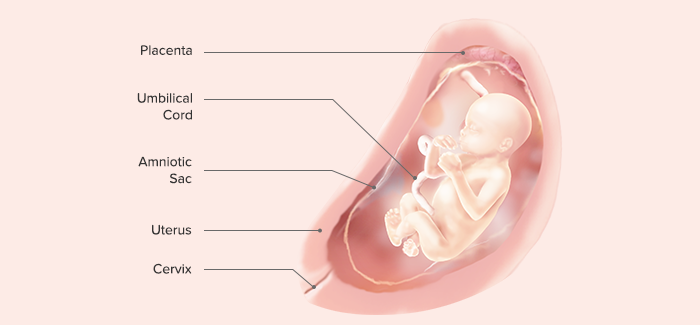

X. End of 40th Gestational Week (Third Trimester)

Length: 48–52 cm (crown to rump, 35–37 cm)

Weight: 3000 g (7–7.5 lb)

The fetus

kicks actively, hard enough to cause the mother considerable discomfort.

Fetal hemoglobin begins its conversion to adult hemoglobin. The conversion is so rapid that, at birth, about 20% of hemoglobin will be adult in character.

Vernix caseosa is fully formed.

Fingernails extend over the fingertips.

Creases on the soles of the feet cover at least two-thirds of the surface